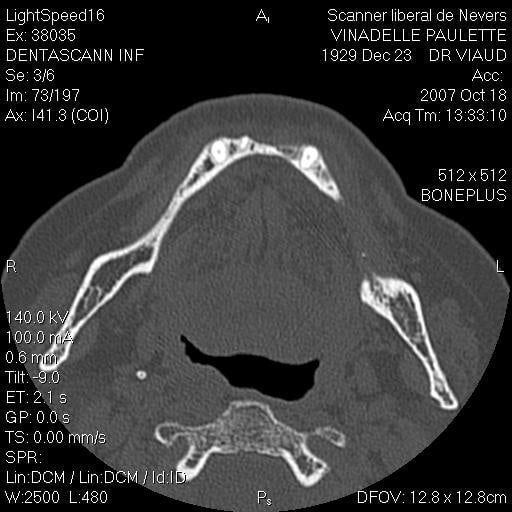

Je suis désolé mais le seul problème que j’ai eu sur un maxillaire inférieure (celui que j’ai mis en photo d’ailleurs) c’est une rupture de la table interne en 33 34 (suite à un mouvement inopportun de la patiente, ce que j’aurais du prévoir) j’ai repris le cas 3 mois plus tard et no problème.

scan te montrant la façon dont je contourne les obstacles